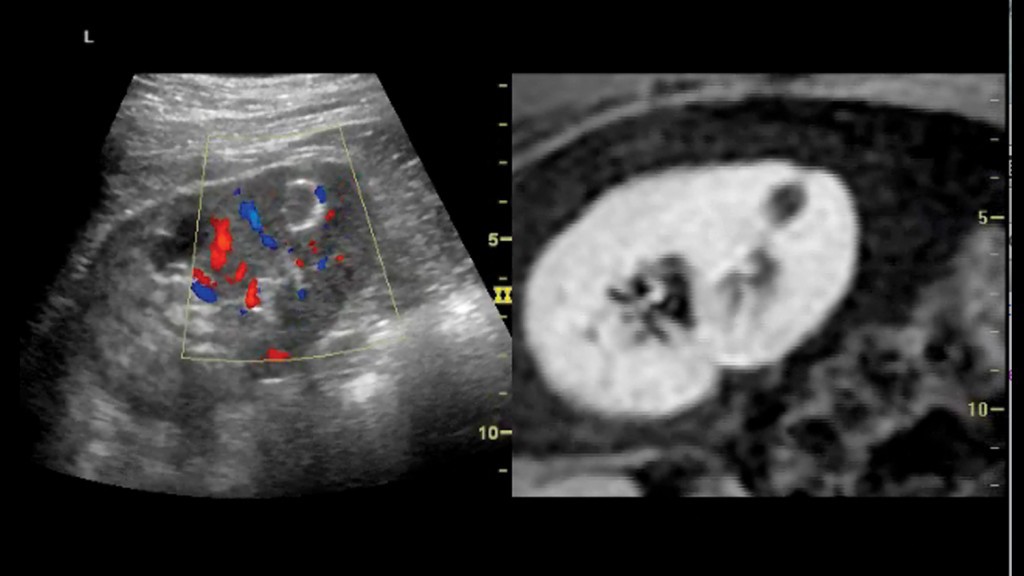

其二:容積導航技術 LOGIQ E9使軍事領域最前沿的容積導航、GPS技術在醫學領域得到瞭應用,容積導航技術是將實時超聲圖像與前次檢查獲得的CT、MR或PET圖像融合在一起,虛擬掃描以前的研究數據以匹配實時超聲圖像,將圖像並列或重疊起來進行比較,充分利用每個成像模式的優勢,通過雙定位器幫助醫生對患者的多個病變目標進行實時跟蹤,對腫瘤病灶進行標記追蹤,讓病變位置無處藏身,還可以實現神奇地在CT片上觀察血流!GPS標記的容積導航技術可以標記病灶的位置並幫助計數,並且通過對最佳穿刺角度的追蹤定位,避免碰到神經血管等結構,引導介入手術的完成,進一步提高穿刺診療的精確性與安全性。LOGIQ E9還可以使用超聲進行療效跟蹤,幫助患者減少CT用量,避免放射劑量。